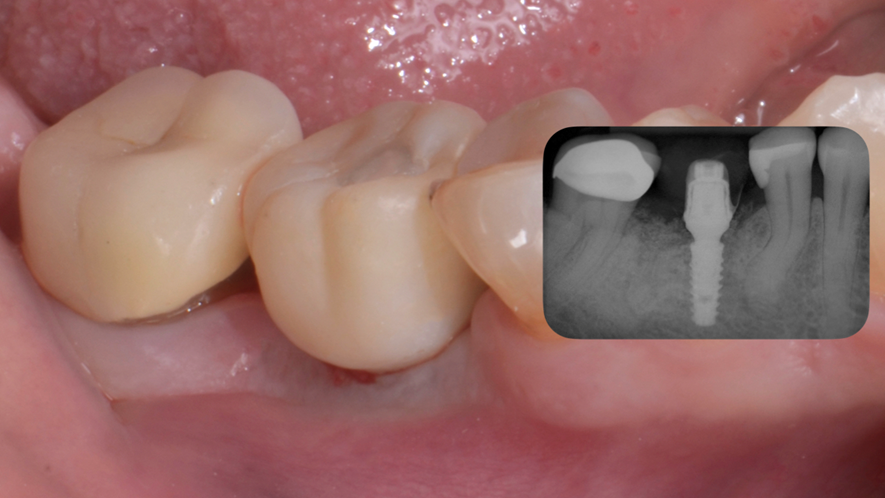

Paciente apresentava um espaço edêntulo posterior na região do dente 46 e, segundo informações colhidas, tinha muita dificuldade na mastigação. Neste caso, foi realizada uma cirurgia virtualmente guiada com guia prototipada e a instalação de um implante Maestro 3,5x11mm e uma carga imediata utilizando o pilar Ideale 4.5x4x2,5 e a coifa provisória de titânio do pilar ideale, para capturar uma coroa provisória CAD/CAM.

Iniciamos o planejamento com o escaneamento intraoral e uma tomografia computadorizada cone beam da mandíbula. De posse das informações, foi realizado o planejamento virtual do implante no Exoplan (Exocad) e o desenho e impressão da guia cirúrgica, bem como de uma coroa provisória CAD/CAM. A cirurgia guiada foi realizada com o Kit Implaguide CM 3.5, seguindo a sequência de fresas preconizadas pela Implacil De Bortoli. Foi instalado o implante Maestro de 3,5x11mm (Figura 1) e, logo após, o pilar Ideale 4,5x4x2,5. A coroa provisória CAD/CAM foi capturada utilizado a coifa provisória de titânio do pilar ideale(Figura 2). Após 60 dias de pós-operatório, a coroa provisória foi removida e observada em excelente perfil de emergência (Figura 3). Solicitamos uma nova tomografia e começamos a planejar a coroa definitiva, num fluxo restaurativo 100% digital com o iTero.